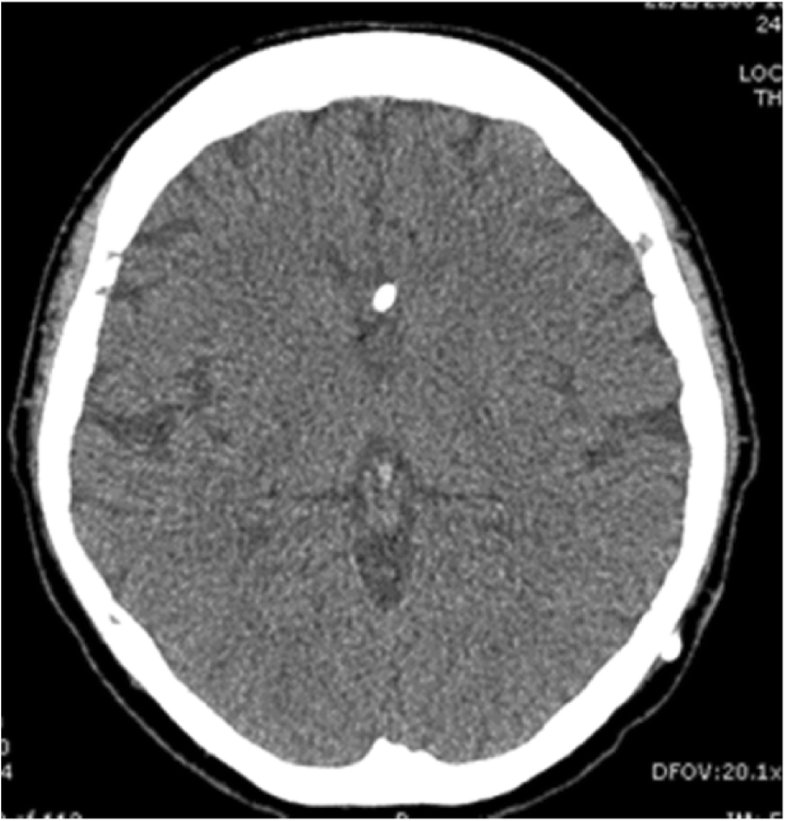

PPT VP Shunts PowerPoint Presentation, free download ID3387790 Shunt Infection Vs Meningitis Aseptic meningitis is the most common form of meningitis with an annual incidence of 7.6 per 100,000 adults. Shunt infections are associated with higher rates of revision, recurrence of infection, ventriculitis, meningitis, and. Cerebrospinal fluid (csf) shunts are used in the setting of hydrocephalus to divert csf to another part of the body for absorption. Symptoms and signs of peritonitis. Shunt Infection Vs Meningitis.